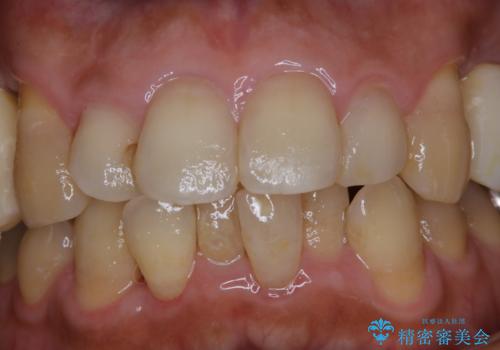

invisalign治療中にPMTCできれいな口元に

- インビザラインでのマウスピース矯正中の方です。矯正中にも定期的なクリーニングを希望とのことでした。PMTC30分コースを行いました。

矯正治療中もPMTCを定期的に行い、専門的な機械でしっかりと汚れを除去することがおススメです。